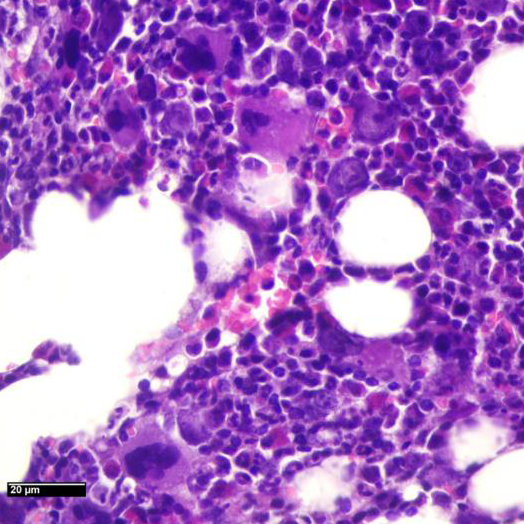

Se realiza punción de médula ósea.

Imágenes Microscopio

C- Cambios citopáticos atribuibles a agente etiológico viral. Sugiero inmunohistoquímica y/o estudio más específico.

MÉDULA ÓSEA HIPERCELULAR CON CAMBIOS CITOPÁTICOS COMPATIBLES CON INFECCIÓN POR PARVOVIRUS

• La morfología típica muestra una médula ósea hipocelular, no como en este caso; pero las características citológicas de los eritroblastos, resaltadas en la coloración de Giemsa, que muestran macrocariosis e inclusiones nucleares; apoyadas por los hallazgos de la PCR confirman el diagnóstico.